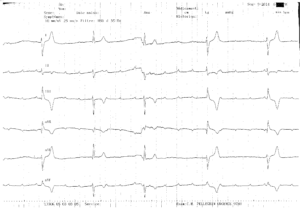

Le rythme jonctionnel ou ventriculaire d’échappement chez un patient en BAV III est généralement régulier, l’électrocardiogramme montrant la dissociation atrio- ventriculaire et la présence d’une bradycardie ventriculaire régulière avec des complexes QRS monomorphes. Parfois, l’échappement peut être instable, son activité se ralentissant ou s’interrompant brutalement, ce qui occasionne la survenue de symptômes plus ou moins graves en fonction de la durée de la pause et pouvant aller jusqu’à la mort subite. Ce tracé montre le caractère labile de l’échappement jonctionnel de ce patient. Quand il est présent, le QRS est relativement fin, la fréquence est lente mais permet toutefois d’assurer une hémodynamique correcte. Quand cet échappement ne s’exprime plus, un second foyer d’échappement ventriculaire plus bas situé prend le relais avec des QRS larges et une fréquence plus lente occasionnant la survenue de symptômes et suggérant un risque majeur de mort subite.

Ce patient a bénéficié de la pose d’un stimulateur cardiaque en urgence.